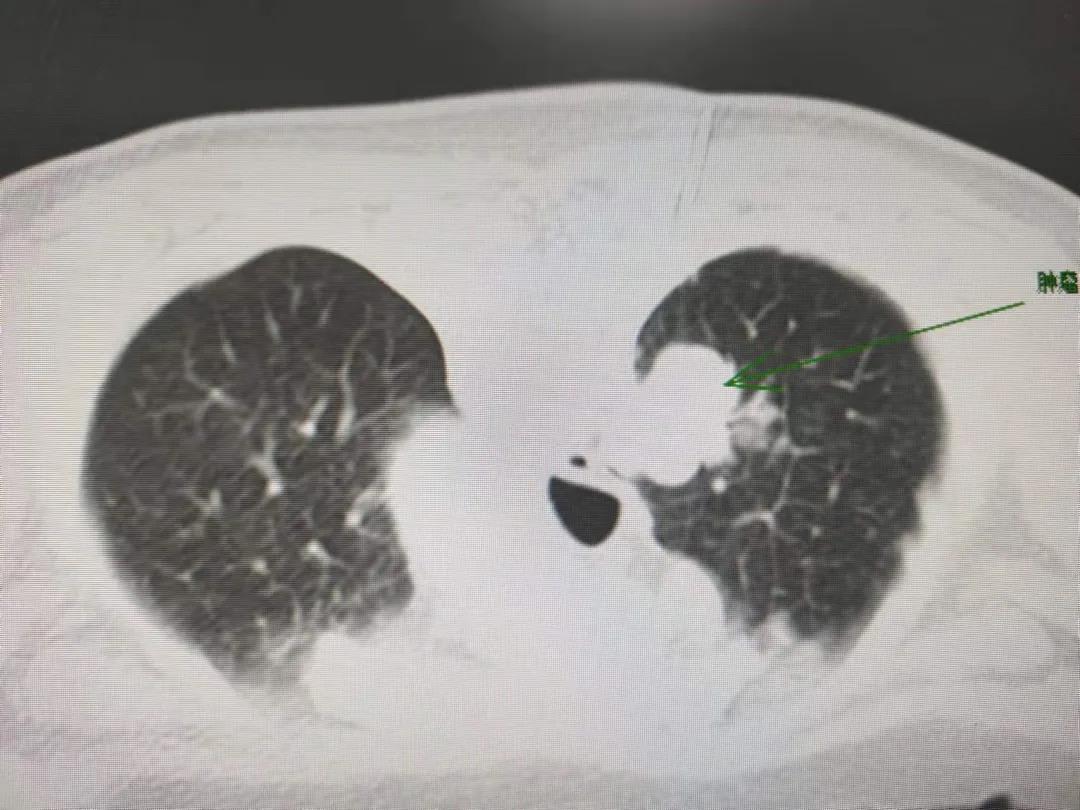

入院后查胸部CT提示右肺上叶占位,行胸部增强CT恶性可能性大。北京驻延呼吸与危重症医学科专家杨洋,谢加利主任,艾克东副主任和影像科王保奇主任进行了充分的阅片讨论:患者胸部瘤体血供丰富,肿瘤靠近脊柱旁,距离胸前壁距离太远,只能选择俯卧位背部穿刺,患者瘤体最大直径3cm,右肺上叶活动度很大,加之患者年事已高并患有帕金森综合征,间断性发作,后背穿刺有肋间动静脉、肋骨及侧突的阻挡,定位难度较大。根据既往临床经验,术中发生大咯血及血胸的风险非常高,因而对穿刺技术的要求非常高。

穿刺活检术中影像

经过与患者及家属充分沟通并征得同意后,呼吸与危重症医学科团队和影像科团队密切配合,在谢加利主任指导下成功为任奶奶实施了CT引导下经皮肺穿刺活检术。

术后病理结果确诊为肺腺癌,帮助患者明确了诊断。